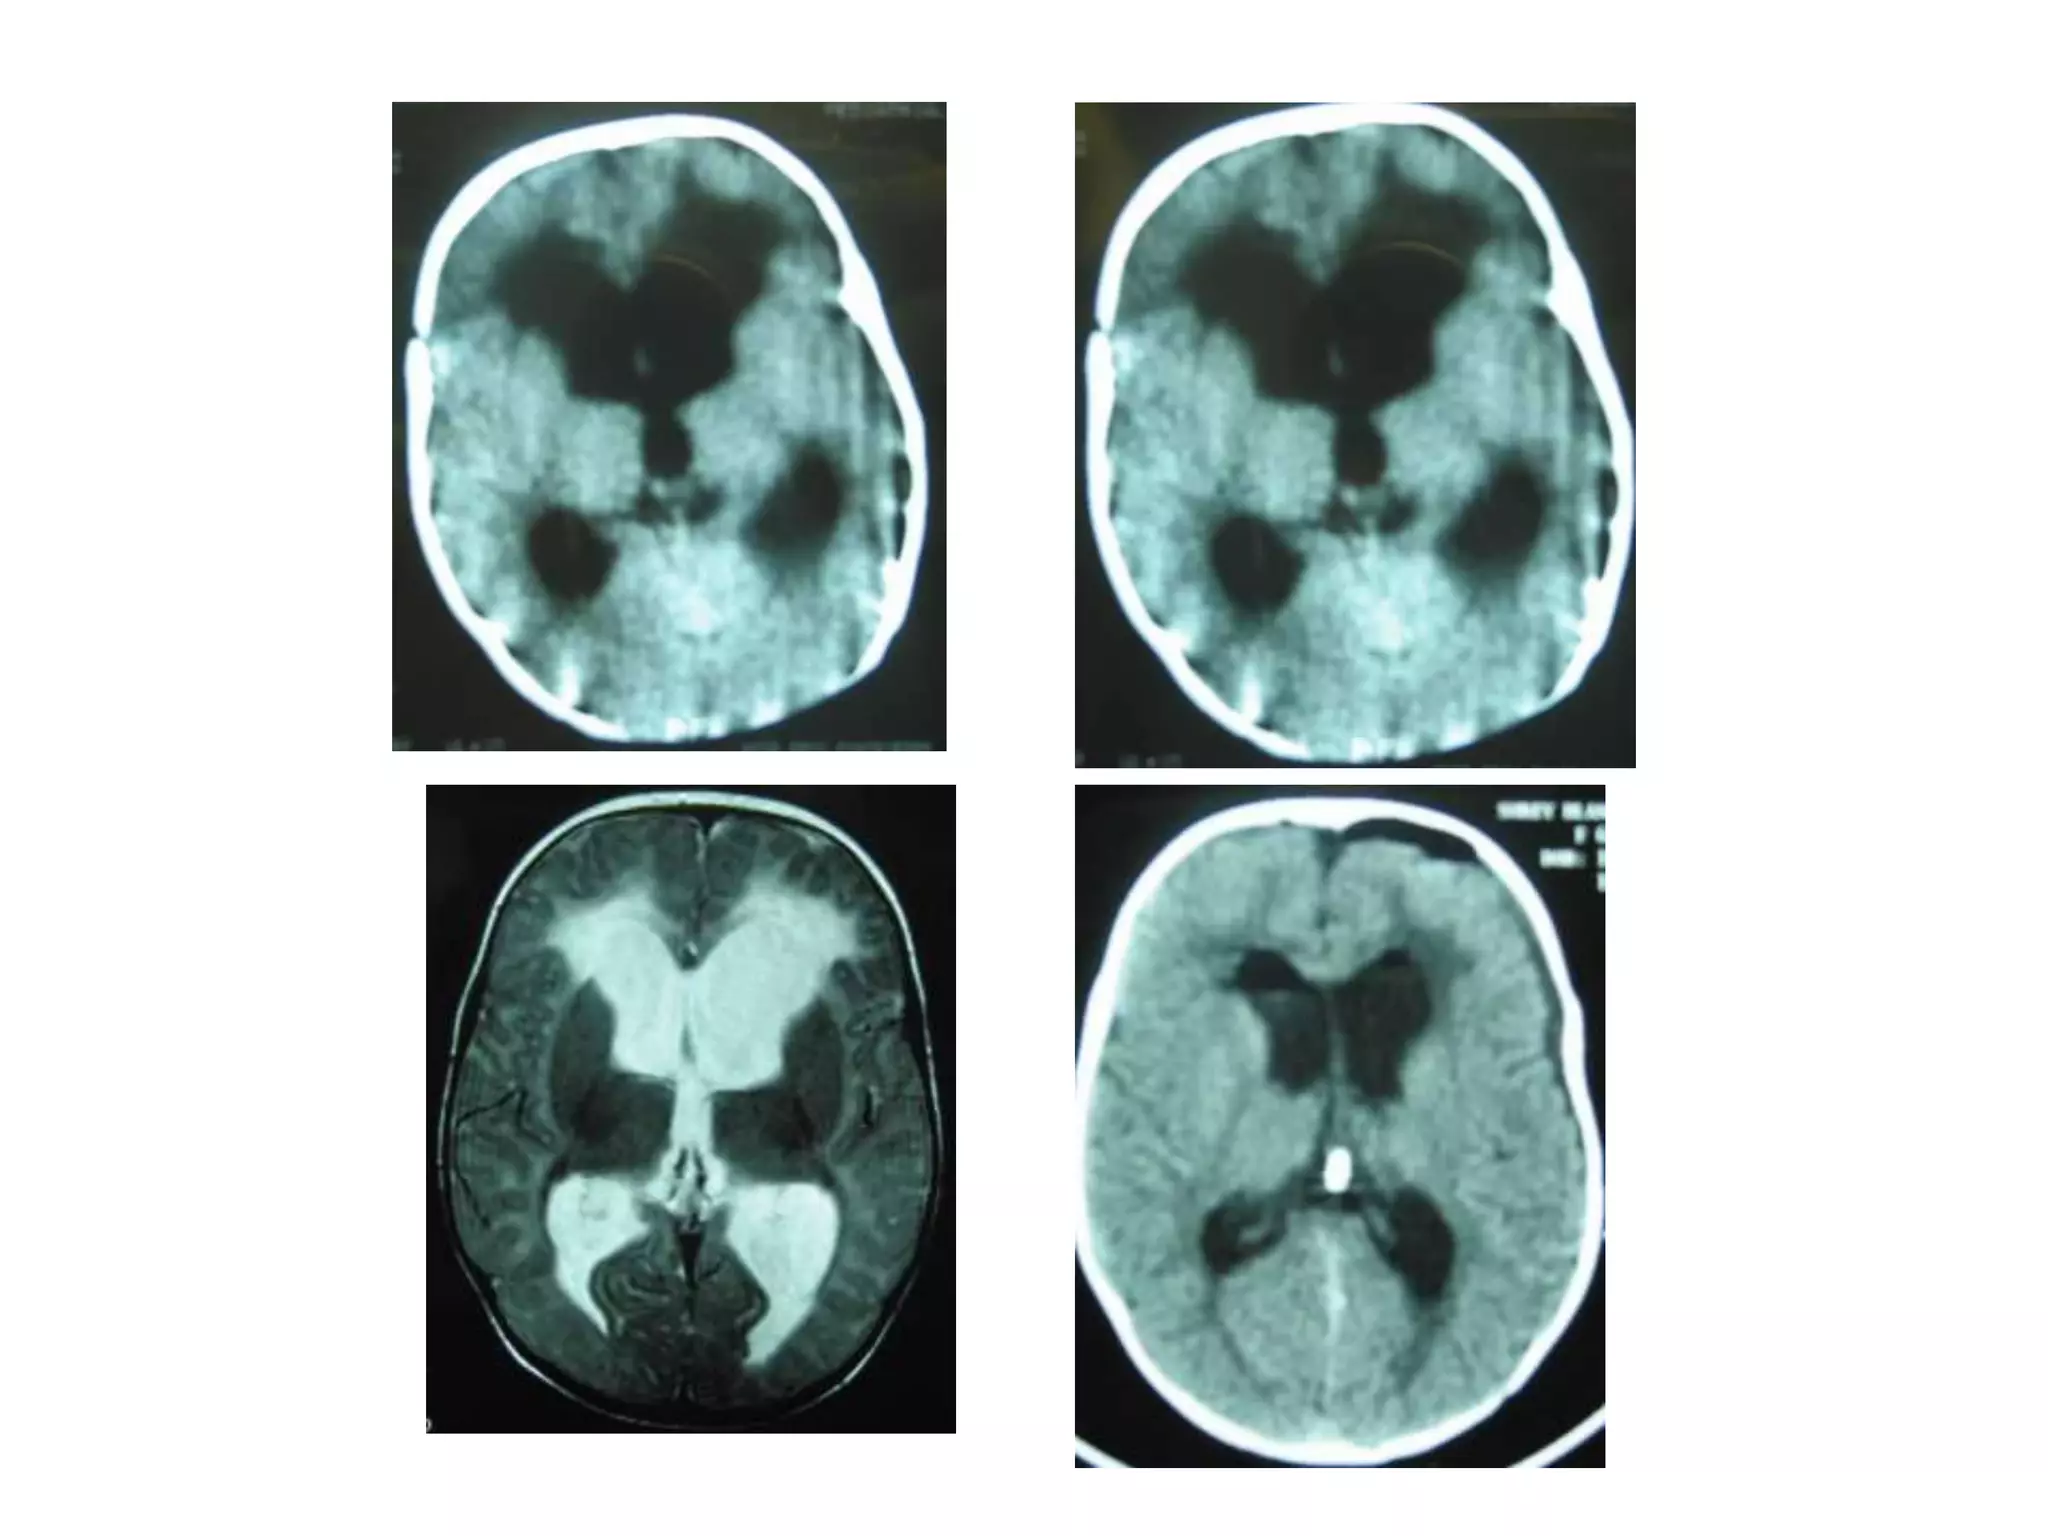

Interstitial oedema:-

• CSF pushed into extracellular space in

Cytotoxic edema:

• This is due to the derangement in cellular metabolism

resulting in inadequate functioning of the sodium and

potassium pump in the glial cell membrane.

As a result there is cellular retention of sodium and water.

There are swollen astrocytes in grey and white matter.

EDEMA           VASOGENIC            CYTOTOXIC         INTERSTITIAL

1.PATHOLOGY     ↑CAPILLARY           CELLULAR          ↑BRAIN WATER DUE TO

PERMEABILITY         SWELLING          ↓ABSORPTION OF CSF

2.LOCATION OF   WHITE MATTER         GRAY&WHITE        PERIVENTRICULAR WHITE

EDEMA                                MATTER            MATTER

3.COMPOSITION   PLASMA FILTRATE Ĉ    ↑IC WATER & Na      CSF

PLASMA PROTEINS

4.ECF                  ↑↑               ↓                  ↑↑

5.CAUSES        TRAUMA, TUMOUR,      INFARCTS(EARLY)   OBSTR/COMMUNICATING

ABSCESS,INFARCT(LATE WATER             HYDROCEPHALOUS

STAGES)              INTOXICATION

6.STEROIDS        ++                    ___                _____

7.MANNITOL        ++                    ++                 _____